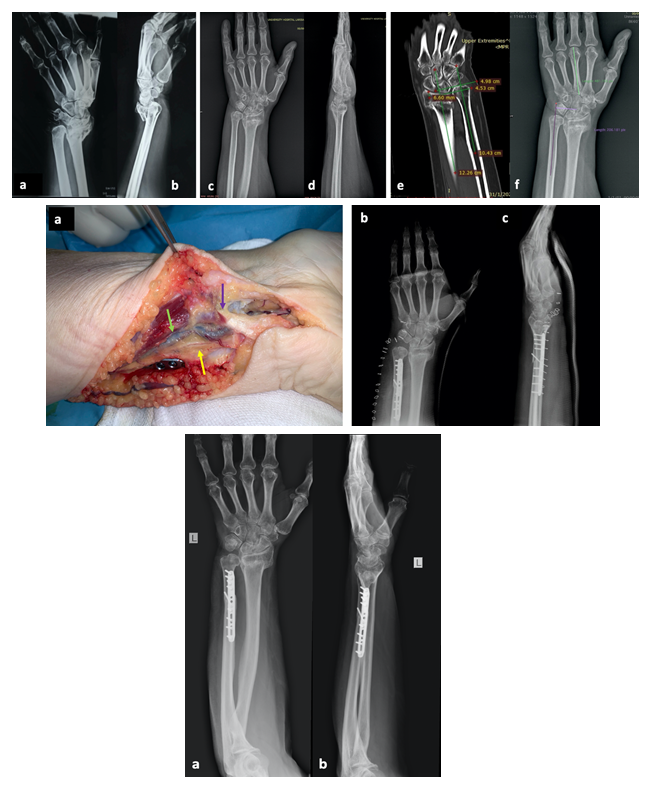

Ulnar Nerve Neuropathy after Distal Radius Fracture Malunion. Uncommon Intra-Operative Findings and a Review of the Literature

Efstratios D. Athanaselis, Fotios Papageorgiou, Dimitrios Deligeorgis, Konstantinos N. Malizos, Sokratis E. Varitimidis

International Journal of Innovative Research in Medical Science·August 1, 2020